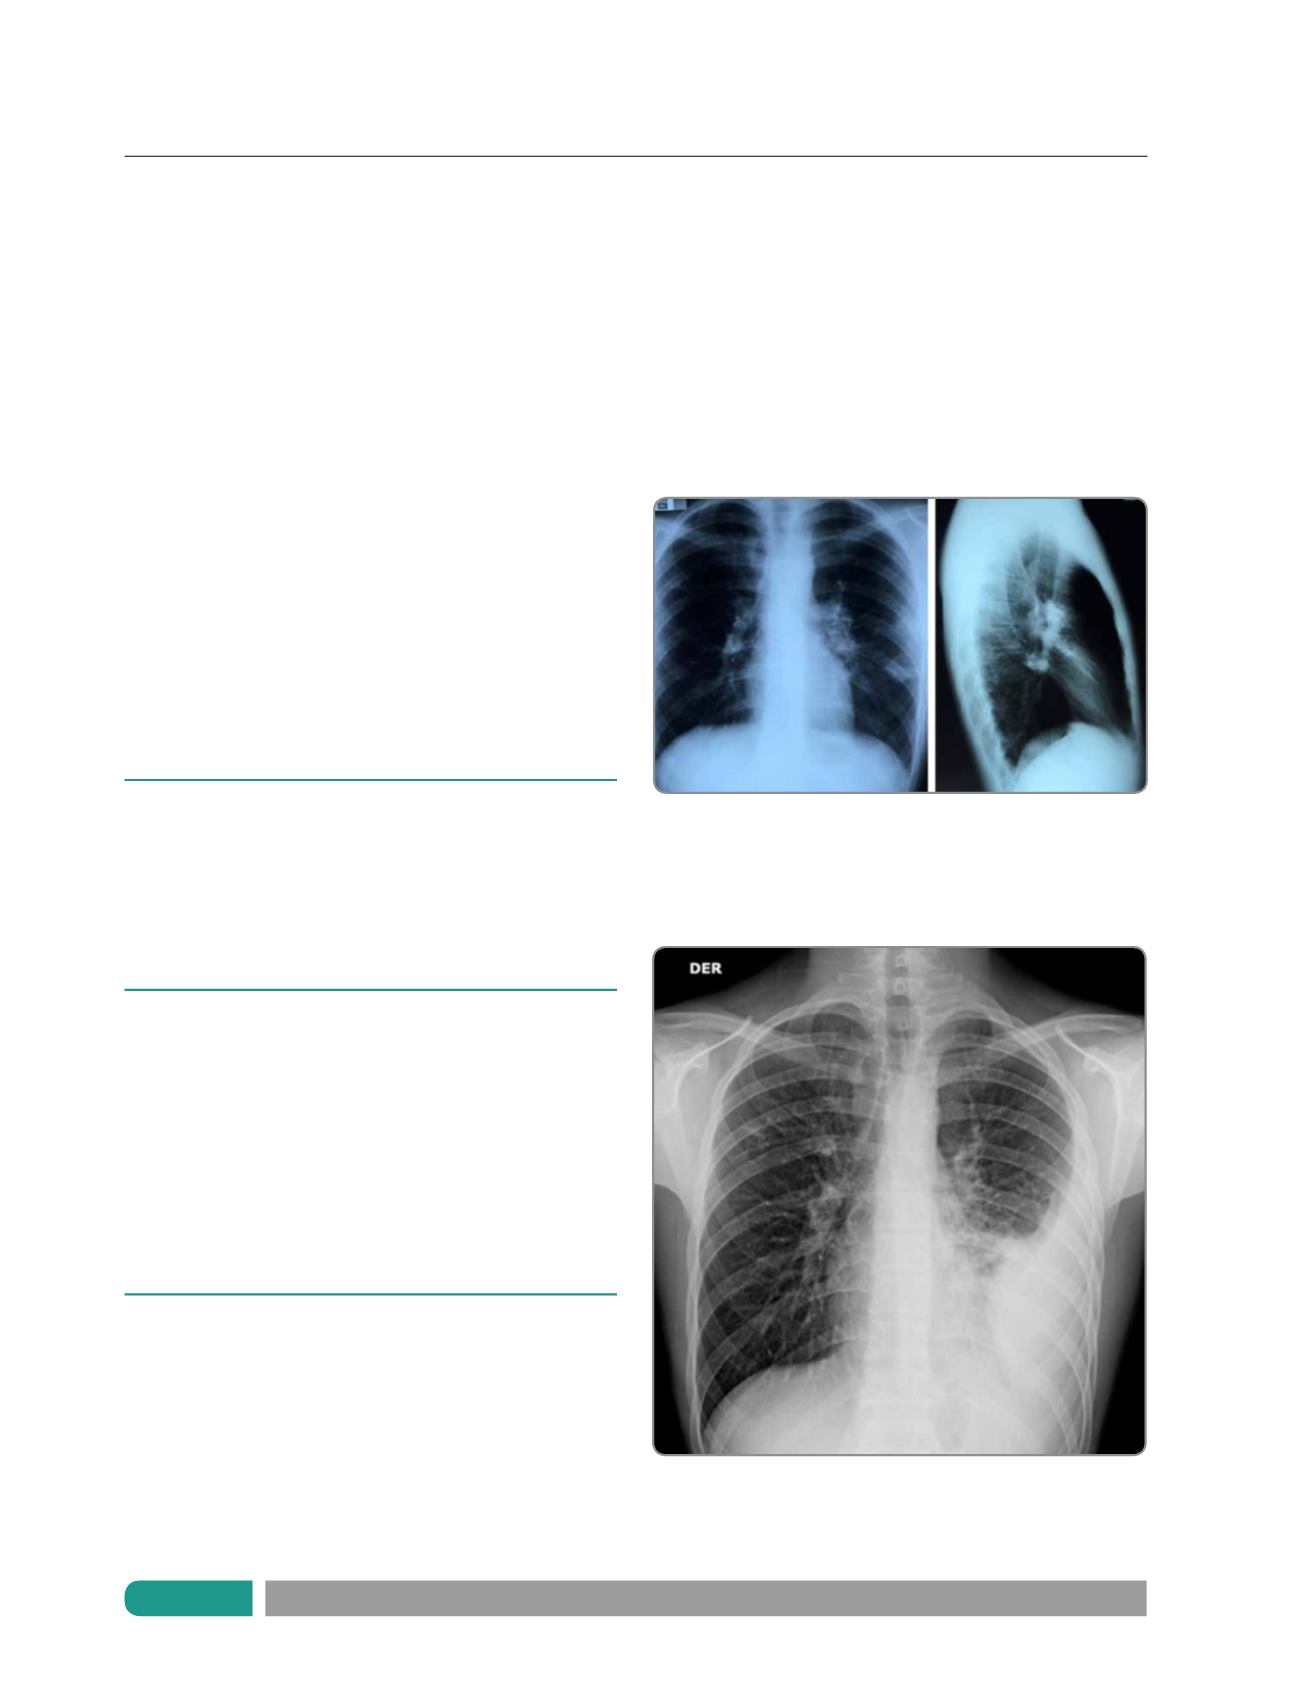

Figura 1a.

Radiografía de tórax, proyección frontal y lateral. Se observa

foco de condensación en relación al tercio medio del campo pulmonar

izquierdo, asociado a leve ensanchamiento del hilio izquierdo, de

contorno convexo, sugerente de adenopatias.

Figura 1b.

Radiografía de torax frontal. Se observa extenso derrame

pleural que ocupa los dos tercios inferiores del campo pulmonar

izquierdo